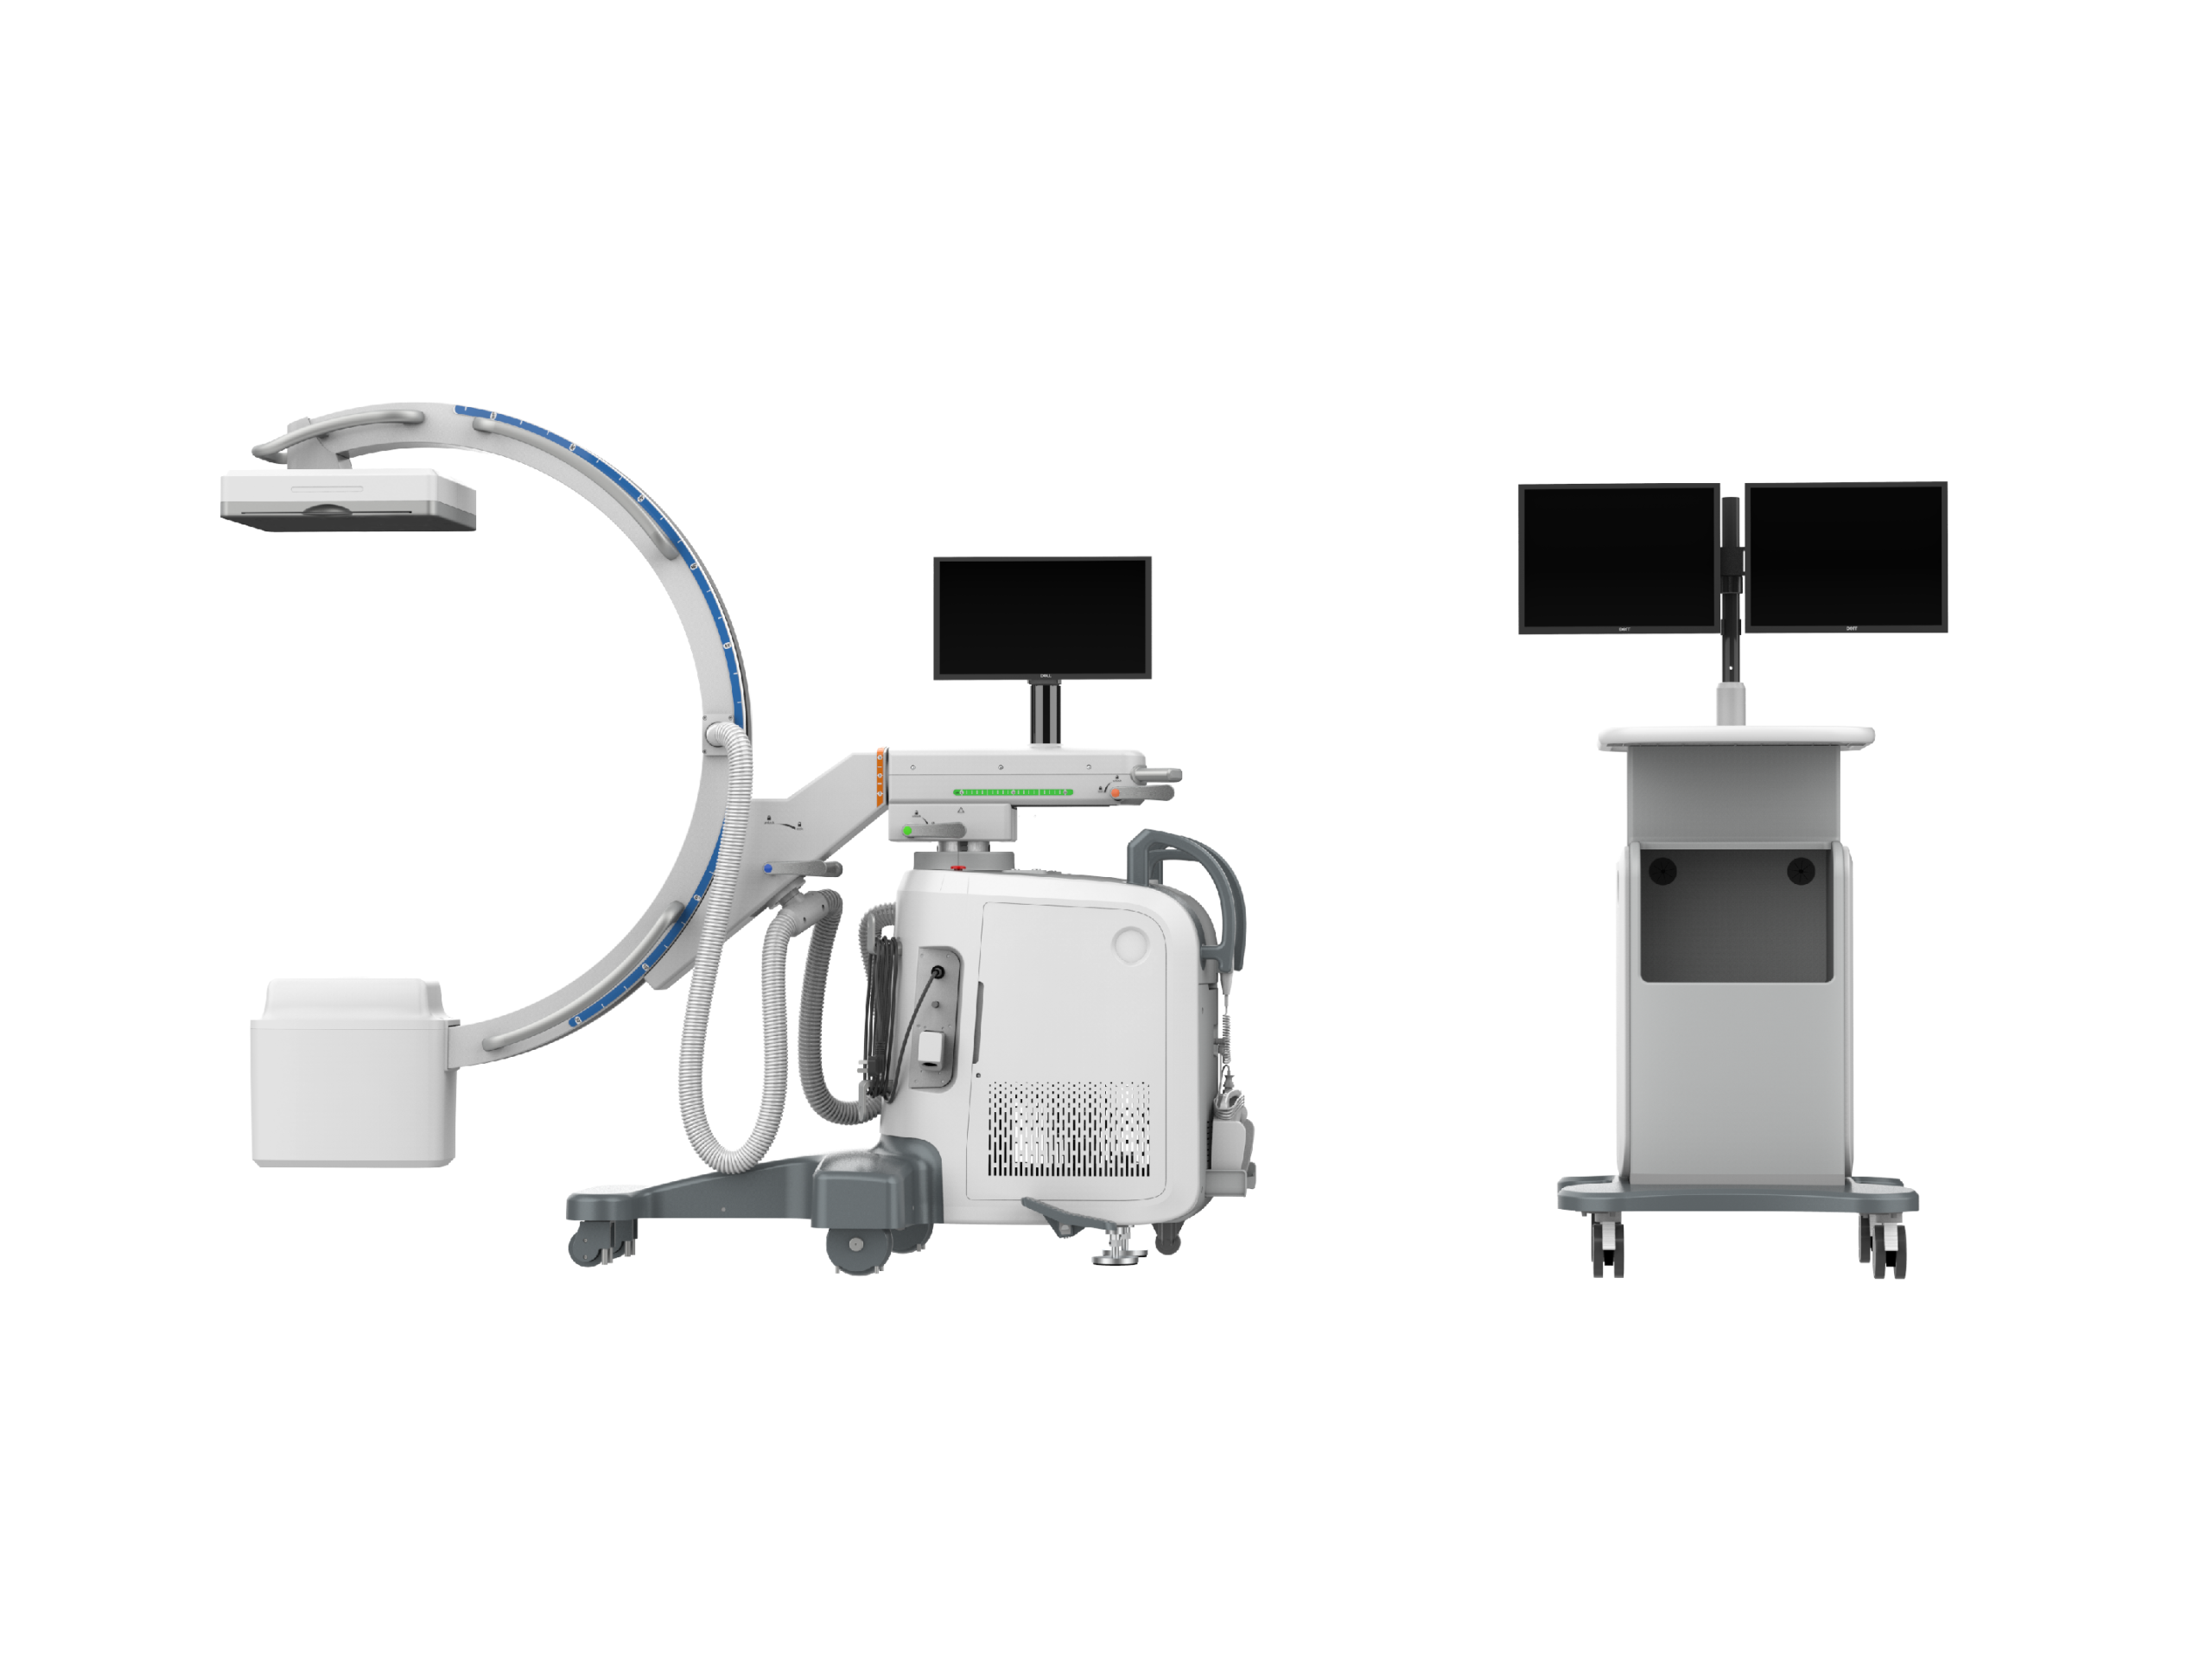

DMCA02 Best Price Digital Touch Monitor C-arm X Ray System For Hospital Operating Room Digital C-Arm Radiography

| Product Name | DMCA02 Best Price Digital Touch Monitor C-arm X Ray System For Hospital Operating Room Digital C-Arm Radiography |

| Size | 2120*965*450-740mm |

| Packing Size of set | 2090*1100*430mm (1 set per carton) |

| Loading capacity | 250kg / 551lbs |

1. Features:

1) Electric source (V): AC110/220

2) Power(kw): 15

3) Spatial Resolution(lp/mm): 3.3

4) Pixel Matrix( pixels): 1024×1024

5) Pixel Pitch(um): 105

6) Removable grid: Yes

7) Active area(mm): 307.2 x307.2

8) Data Interface: 10G Ethernet

9) ms range (ms): 10-1600

10) Mas range(mAs): 0.2-100

11) Focal spots(mm): 0.3/0.6

12) SID(mm): 1080

13) Free space in arc( mm): 884

14) Depth in arc( mm): 640

15) Orbital rotation(°): 150 (117/-33)

16) Lateral rotation(°): 360 (±225)

17) wig/wag(°): ±15